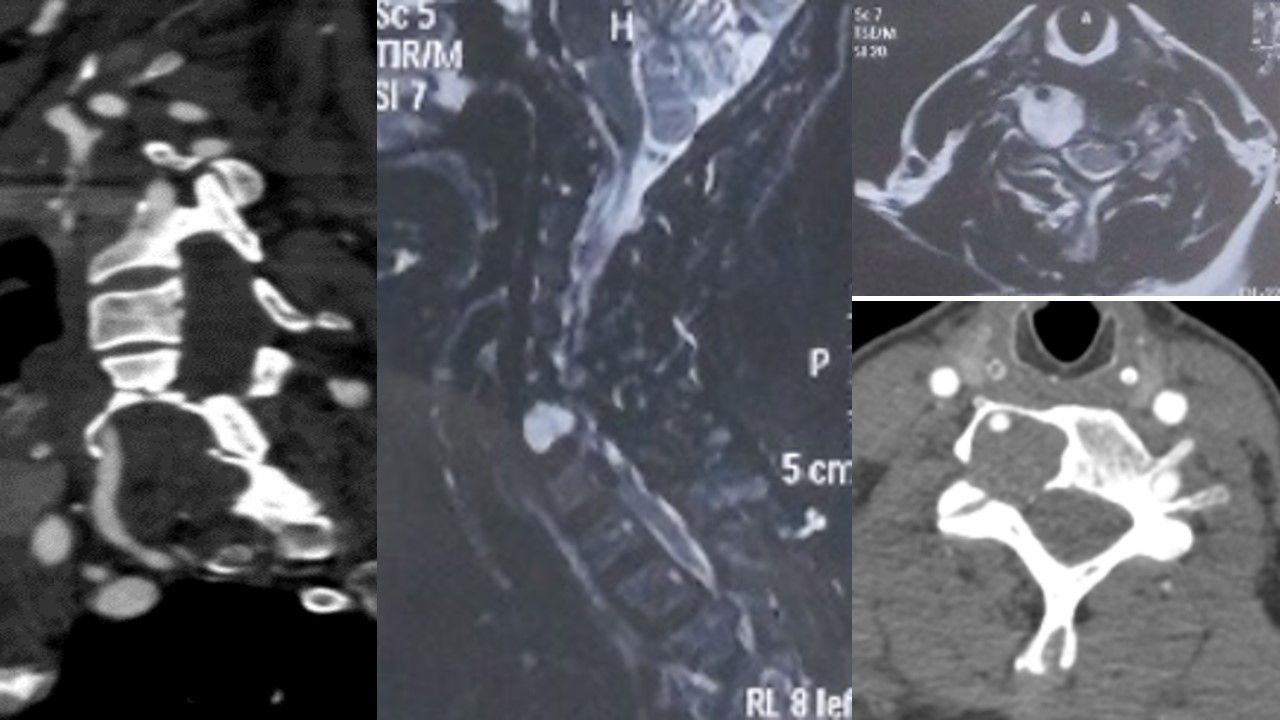

患者刘女士,63岁,体检时意外发现颈部占位性肿物,无自觉症状,颈部无外观异常,在当地医院诊治后考虑手术风险极大,建议转上级医院。患者来西安后,辗转各大医院,后来我院,收治于脊柱与骨肿瘤病区王栋主任团队。入院后,秦杰副主任医师作为主管医生,为患者安排了精细化检查,确定肿物位于颈6/7右侧椎间孔、颈6右侧横突孔区域,大小约3.8×2.3cm,考虑良性肿瘤,但邻近的右侧椎动脉受压明显并包绕肿瘤前缘,关系紧密。众所周知,椎动脉是是供应脑干、小脑和大脑后循环的主要动脉,一旦损伤,可能引起致命的局部出血及脑缺血;另一方面,椎间孔内存在掌管上肢运动感觉的脊神经,一旦损伤,可能引起严重上肢功能障碍,影响患者生存质量;此外,还需考虑肿瘤复发等情况。在如此狭小的操作空间,切除紧邻动脉、脊髓神经的肿瘤,稍有不慎即可导致永久瘫痪甚至危及生命,这如同在钢丝上跳华尔兹,其难度和风险可想而知!

术前影像